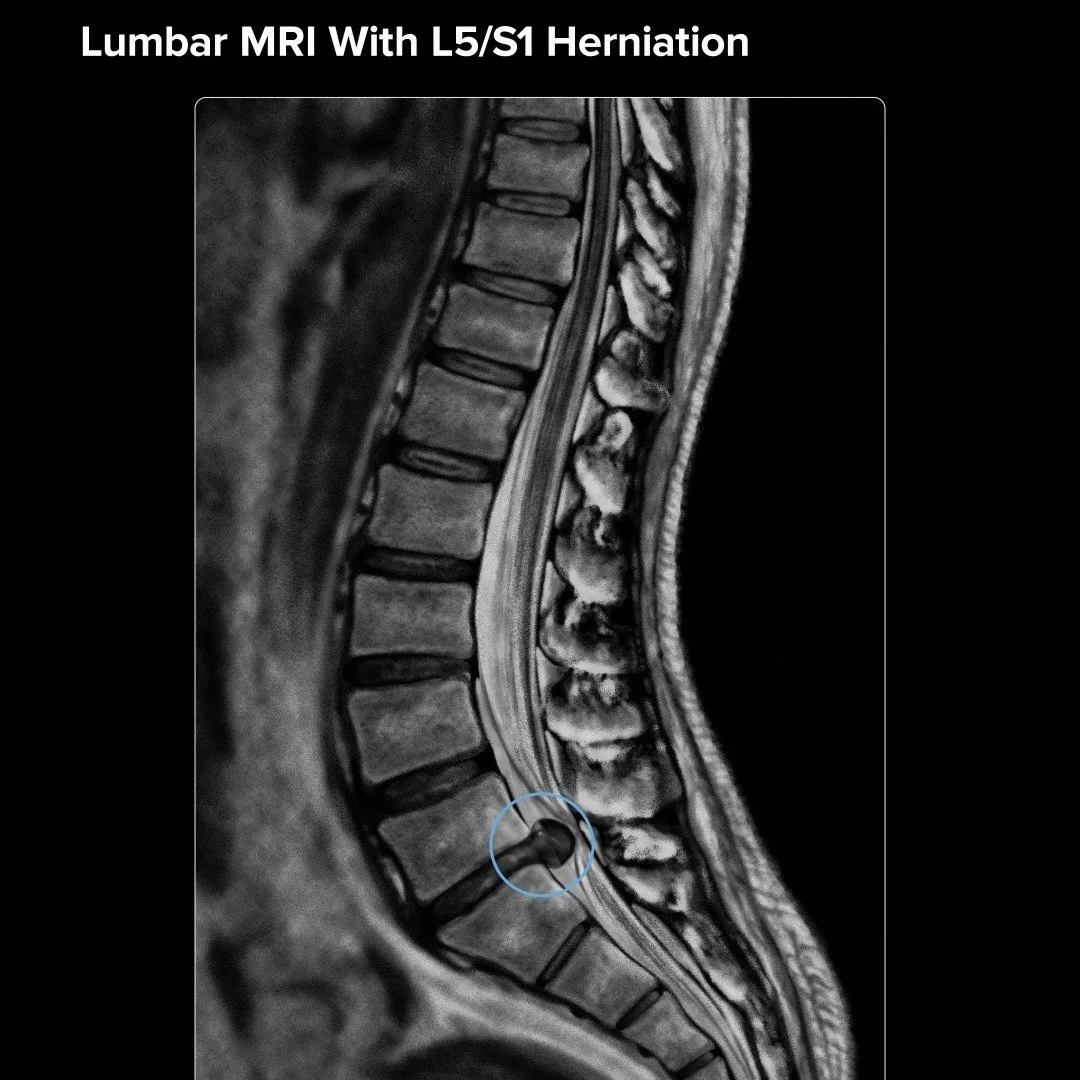

Spinal Conditions

Spinal Treatments